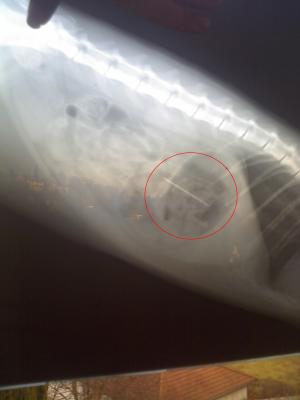

Ein Röntgenbild von ihrer Katze, kurz nachdem diese eine Nadel verschluckt hat, blödes Tier.

Am selben Tag noch zum Tierarzt, Bauch aufschneiden, Magen öffnen (zum Glück nur leicht) und Nadel wieder raus.